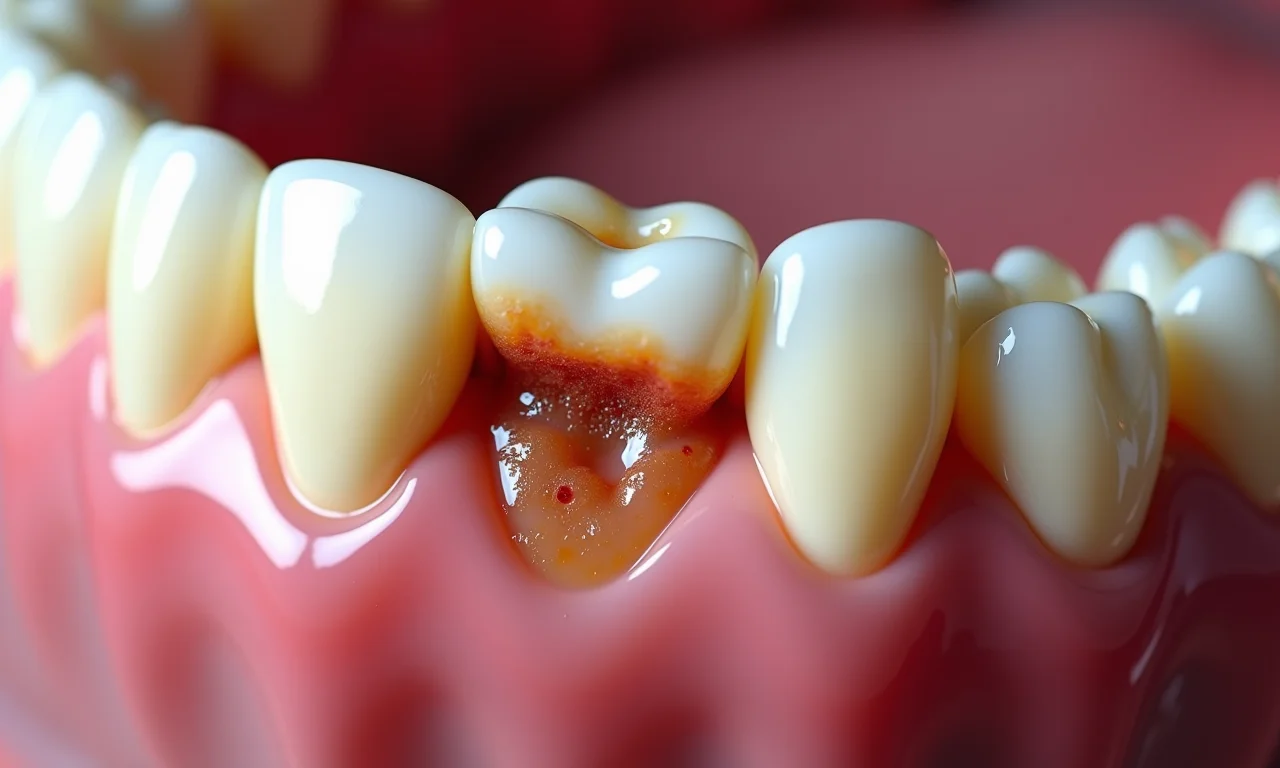

Cáries e Doenças Periodontais

A posição dos sisos, muitas vezes de difícil acesso, pode dificultar a higiene e favorecer o acúmulo de placa bacteriana. Isso aumenta o risco de cáries e doenças periodontais, que podem comprometer a saúde dos dentes vizinhos. Vamos combinar, ninguém quer isso!